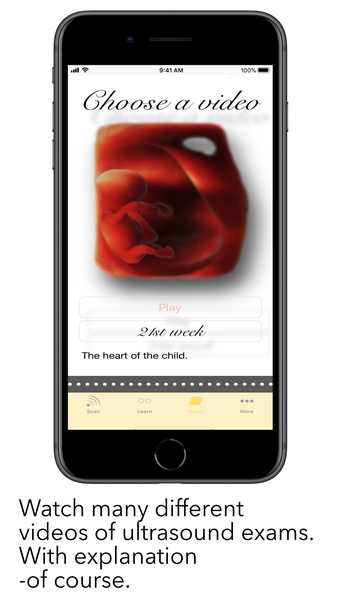

The app is divided into three different modes: Scan, Learn, and Watch. In Scan mode, users can scan a baby with labelling mode turned on to see all the important structures colored. This helps expecting parents understand the shown structures better and compare the ScanBaby image to their own ultrasound image. In Learn mode, users are taught about the developmental stages of their child through artfully crafted 3D scans of real babies that can be moved around. The scans come with labelling as well. Finally, in Watch mode, the app includes many different ultrasound videos that users might see during their own examination, with a short explanation of what can be seen.